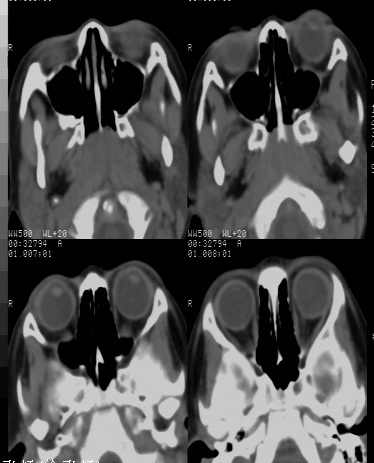

女 5岁 夜间打鼾数年 本人第一次遇到这样的病人,不知是不是鼻咽增殖体肥大?需不需要做手术,请同行给予指导。

典型的鼻咽增殖体肥大

鼻咽腔顶壁及后壁软组织明显肿胀,厚度约2.5cm,鼻咽腔气道轻度狭窄,加之临床病史,支持腺样体肥大。

还可以用鼻咽侧位片测量鼻咽顶部增殖体的厚度和鼻咽腔的宽度,以两者比率来判断儿童增殖体是否肥大。正常时两者比率≤0.60;当比率为0.61~0.70属中度肥大;比率≥0.71属病理性肥大。

结合病史的话,看到鼻烟后顶壁软组织增厚,应该考虑腺样体增大